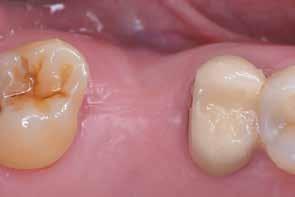

A teljesen digitalizált protetikai munkafolyamat során az Exocad szoftver segítségével (exocad) egy hibrid, csavarrögzített, cirkónium monolit koronát gyártottunk le copaSKY

uni.fit titánalapra (bredent medical). Az implantátum körül a bukkális lágyszövet megfelelő vastagságot és kedvező ínykontúrt mutatott (12. a–b. ábra). Az egyedi ínyformázó eltávolítása után egészséges implantátum körüli lágyrészgallér

értünk el (19. ábra). Az okkluzális nyílást tefloncsíkkal és kompozittal zártuk (20. ábra). Mindezek után, posztoperatív kontroll röntgenfelvétel készült, amely a pótlás megfelelő illeszkedését mutatta (21. ábra). A hat hónapos utánkövetés során jól megfigyelhető a teltebb lágyszöveti profil és a megtartott kresztális csontszint (22–24. ábra)

volt megfigyelhető (13–14. ábra), ezen kívül közvetlenül a műtét előtt intraorális vizsgálatot végeztünk a lágyszöveti profil megállapítása érdekében. Ezt követte a scanbody behelyezése, így digitális lenyomat készült az implantátum pozíciójáról (15. ábra). Ugyanezzel a technikával rögzítettük az antagonista fogívet és a harapást is. Az így kapott STL-fájlokat digitálisan továbbítottuk a fogtechnikai laboratóriumba. A titánalapra PMMA ideiglenes koronát készítettünk a proximális és marginális illeszkedés ellenőrzése érdekében, valamint a megfelelő harapás elérése céljából (16–17. ábra) Miután az összes igazítás elkészült, ismételt vizsgálatot végeztünk. A végleges hibrid csavarrögzítésű, teljes kontúrú cirkóniumkoronát titánalapon erősen polírozott szubgingivális résszel készítettük el, és 25 Ncm nyomatékra húztuk (18. ábra). Kiváló árnyalategyezést és klinikai eredményt